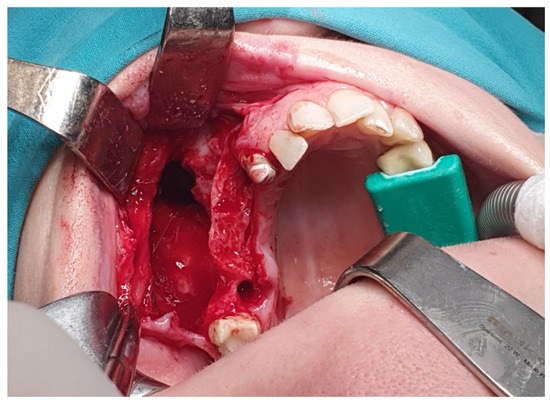

2. Case Presentation